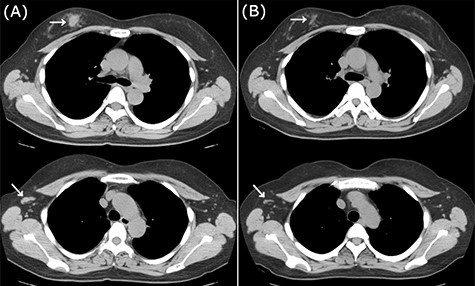

CT images of right breast tumor before and after treatment. (A) Chest CT displaying nodules in the right breast (top, arrowhead) and lymph node swelling in the right axilla (bottom, arrowhead); (B) after administration of NAC, the primary tumor (top, arrowhead) and axillary lymph nodes (bottom, arrowhead) displayed a clear reduction in size.

Neoadjuvant chemotherapy (NAC) was performed with four cycles of 5-fluorouracil (500 mg/m2), epirubicin (100 mg/m2) and cyclophosphamide (500 mg/m2) (FEC100 regimen), which showed a favorable response on imaging (Fig. 2B). She underwent surgery without taxane because she enrolled in a clinical trial (University Hospital Medical Information Network (UMIN) Clinical Trials Registry No.: R000029940) [4]. Postoperative treatment depends on the histopathological results. Based on the patient’s BRCAness score (0.6), she underwent breast-conserving surgery, and axillary lymph node (LN) dissection owing to a positive sentinel node biopsy. Pathological analysis demonstrated almost pCR in the breast and only a few degenerated carcinoma cells remaining in the stroma, with no metastatic carcinoma cells in the dissected LNs. Thus, she was sequentially administered 12 cycles of weekly paclitaxel and 50 Gy of radiotherapy.